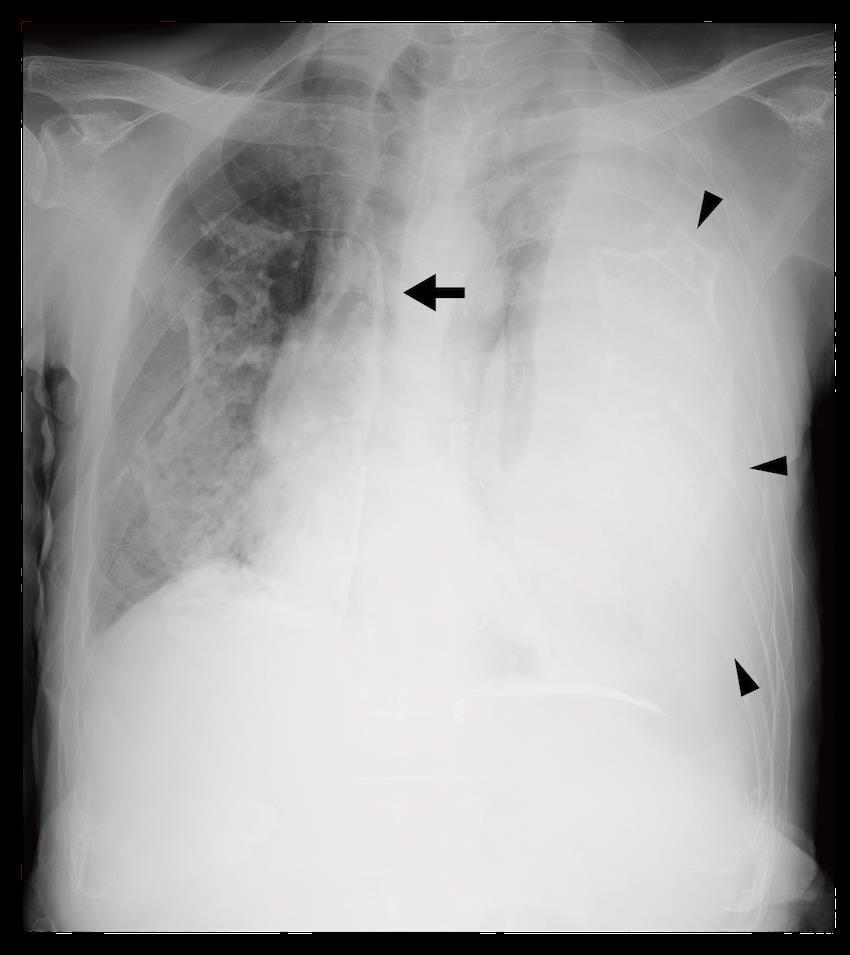

3 4% Ibuprofen 10/10 5 mL 0.25% bupivacaine 0/10

TBSA, total body surface area; PO, oral medication; PTN, posterior tibial nerve; mL, milliliter.